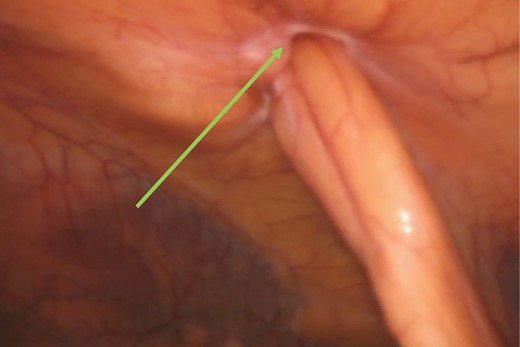

The hernia was repaired laparoscopically through a TAPP mesh repair. Laparoscopic visualization revealed a small umbilical hernia as well as a falciform ligament port site hernia (Fig. 7). The falciform ligament was mobilized and the hernia was reduced into the abdominal cavity (Fig. 8). The peritoneum around the hernia neck was mobilized to clearly expose the neck. The neck was then closed intra-corporeally with an intra-operative V-loc non-absorbable suture™ (Fig. 9). The hernia defect was then covered with an underlay Ventralite™ mesh and secured with Absorbatac™ staples (Fig. 10). The umbilical hernia was not repaired as we had not obtained consent for its repair. This was an intra-operative diagnosis. Her post-operative recovery was uneventful and she was discharged home the same day.

Intra-corporeal suturing of the hernia neck (green arrow) with a V-loc™ suture.